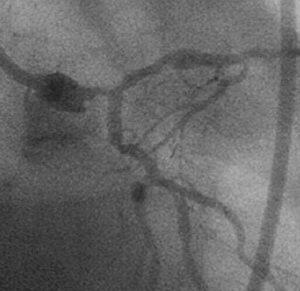

18時をまわった頃でしょうか、最後のad-hoc 症例が何のことはない、D1 95%の

お婆さんでした(fig1)。それまでの複雑病変とはうってかわったsimpleな症例で

す。病変を甘く見た私は、疲れもあって、いつものlong-tipでなく、開けられるま

ま、JL4と、普通のスプリングタイプのワイヤで手技をはじめました(fig2)。バッ

クアップ不足や病変の石灰化もあって、2.5mmバルーンは病変を通過しませんでした

(fig3)。うすいマーカーがご覧になれるでしょうか? ちょっとやな感じです。1.

5mmのバルーンをもう1本あけるのは、支払い能力の関係で不可といわれました。そこ

で、病変のリクロスは簡単だろうし、ガイドのほうが、バルーンよりずっと安価なの

で、long-tipに変えようとおもい、一旦ワイヤを抜きました。

すると、忘れもしない、あの、なんとも言えないイヤな感触がしました。そうです、

ワイヤ断裂です。透視でみると、何とLMT-LADに漂流しておりました(fig4)。目が

点、とはこのことです。CTOでもなんでもなく、特別手荒な操作もしていなかったつ

もりなのに、何でこんな目にあうのだろうと己の運命を呪いました。